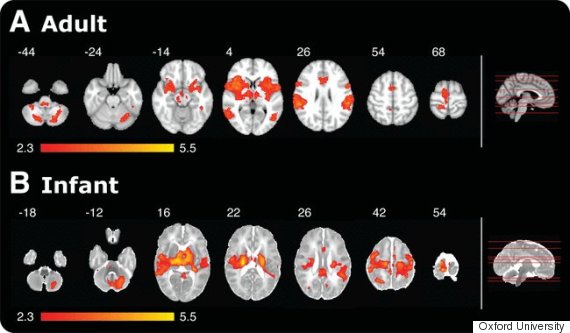

Theo một nghiên cứu mới của trường Đại học Oxford, trẻ sơ sinh vài ngày tuổi đã cảm nhận được sự đau đớn như người lớn. Qua kết quả chụp cộng hưởng từ (MRI), các nhà nghiên cứu thấy khi đau nhẹ, bộ não của trẻ sơ sinh “thắp sáng” tương tự như bộ não của người lớn.

Vậy điều các nhà nghiên cứu tìm thấy là gì? 18 trong số 20 vùng não ở người trưởng thành được kích hoạt khi trải qua cơn đau cũng được hoạt hóa ở trẻ sơ sinh. Điều này cho thấy rằng trẻ sơ sinh không chỉ cảm thấy đau đớn như người lớn mà chúng còn có một ngưỡng chịu đau thấp hơn.